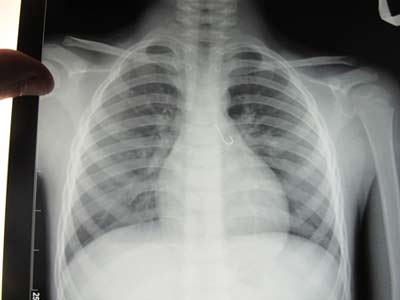

Chiều 16/9, tin từ các BS chuyên khoa Tai - Mũi - Họng, bệnh viện đa khoa Đà Nẵng cho biết: đã phẫu thuật cấp cứu thành công cháu bé 7 tuổi bị mắc lưỡi câu trong phỗi.

Bản chụp X-Quang thấy rõ lưỡi câu mắc trong phổi bệnh nhi

Bệnh nhi N.X.T 7 tuổi, là người dân tộc Cơ tu thường trú tại huyện Nam Trà My, tỉnh Quảng Nam. Trước đó, ngày 10/9, bệnh nhi nhập viện trong tình trạng ngột thở, ho sặc sụa. Qua nội soi cấp cứu, phát hiện 1 lưỡi câu còn nguyên móc, dài 1,5cm mắc ở phổi. Lưỡi câu cắm vào niêm mạc của phế quản. Các bác sĩ đã tiến hành phẫu thuật cấp cứu lấy lưỡi câu ra khỏi phổi bệnh nhi an toàn. Qua theo dõi điều trị, hiện sức khỏe bệnh nhi đã bình phục hoàn toàn.

Điều tra bệnh lý, người nhà bệnh nhi cho biết: trong lúc đi câu cá với các bạn, sợ các bạn giành mất lưỡi câu nên cháu ngậm giấu lưỡi câu trong miệng. Không may, cháu để lưỡi câu tuột luôn xuống họng. Khi cháu bị ngạt thở nguy cấp, người nhà đưa ra viện điều trị mới tá hỏa khi biết lưỡi câu mắc hẳn vào trong phổi. Các bác sĩ chuyên khoa nhận định, rất may cháu bé được cấp cứu kịp thời, không thì khó tránh khỏi nguy cơ thiệt mạng.